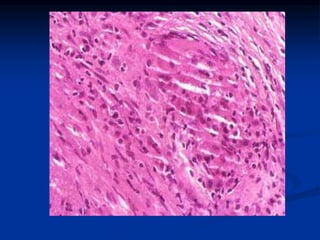

FIEBRE REUMATICA Y CARDIOPATIA

REUMATICA

Enfermedad inflamatoria aguda, de mecanismo inmunitario.

Estreptococo del grupo A beta hemolítico.

Morfología:

En el corazón se observan los cuerpos de Aschoff: focos de

degeneración fibrinoide rodeados de linfocitos principalmente

T , aislados plasmocitos y macrófagos hinchados llamados

células de Anitschkow , estas células son patognomónicas y

poseen abundante citoplasma anfófilo de núcleo central

redondo u oval y cromatina en franja ondulada y estrecha

(células en oruga)